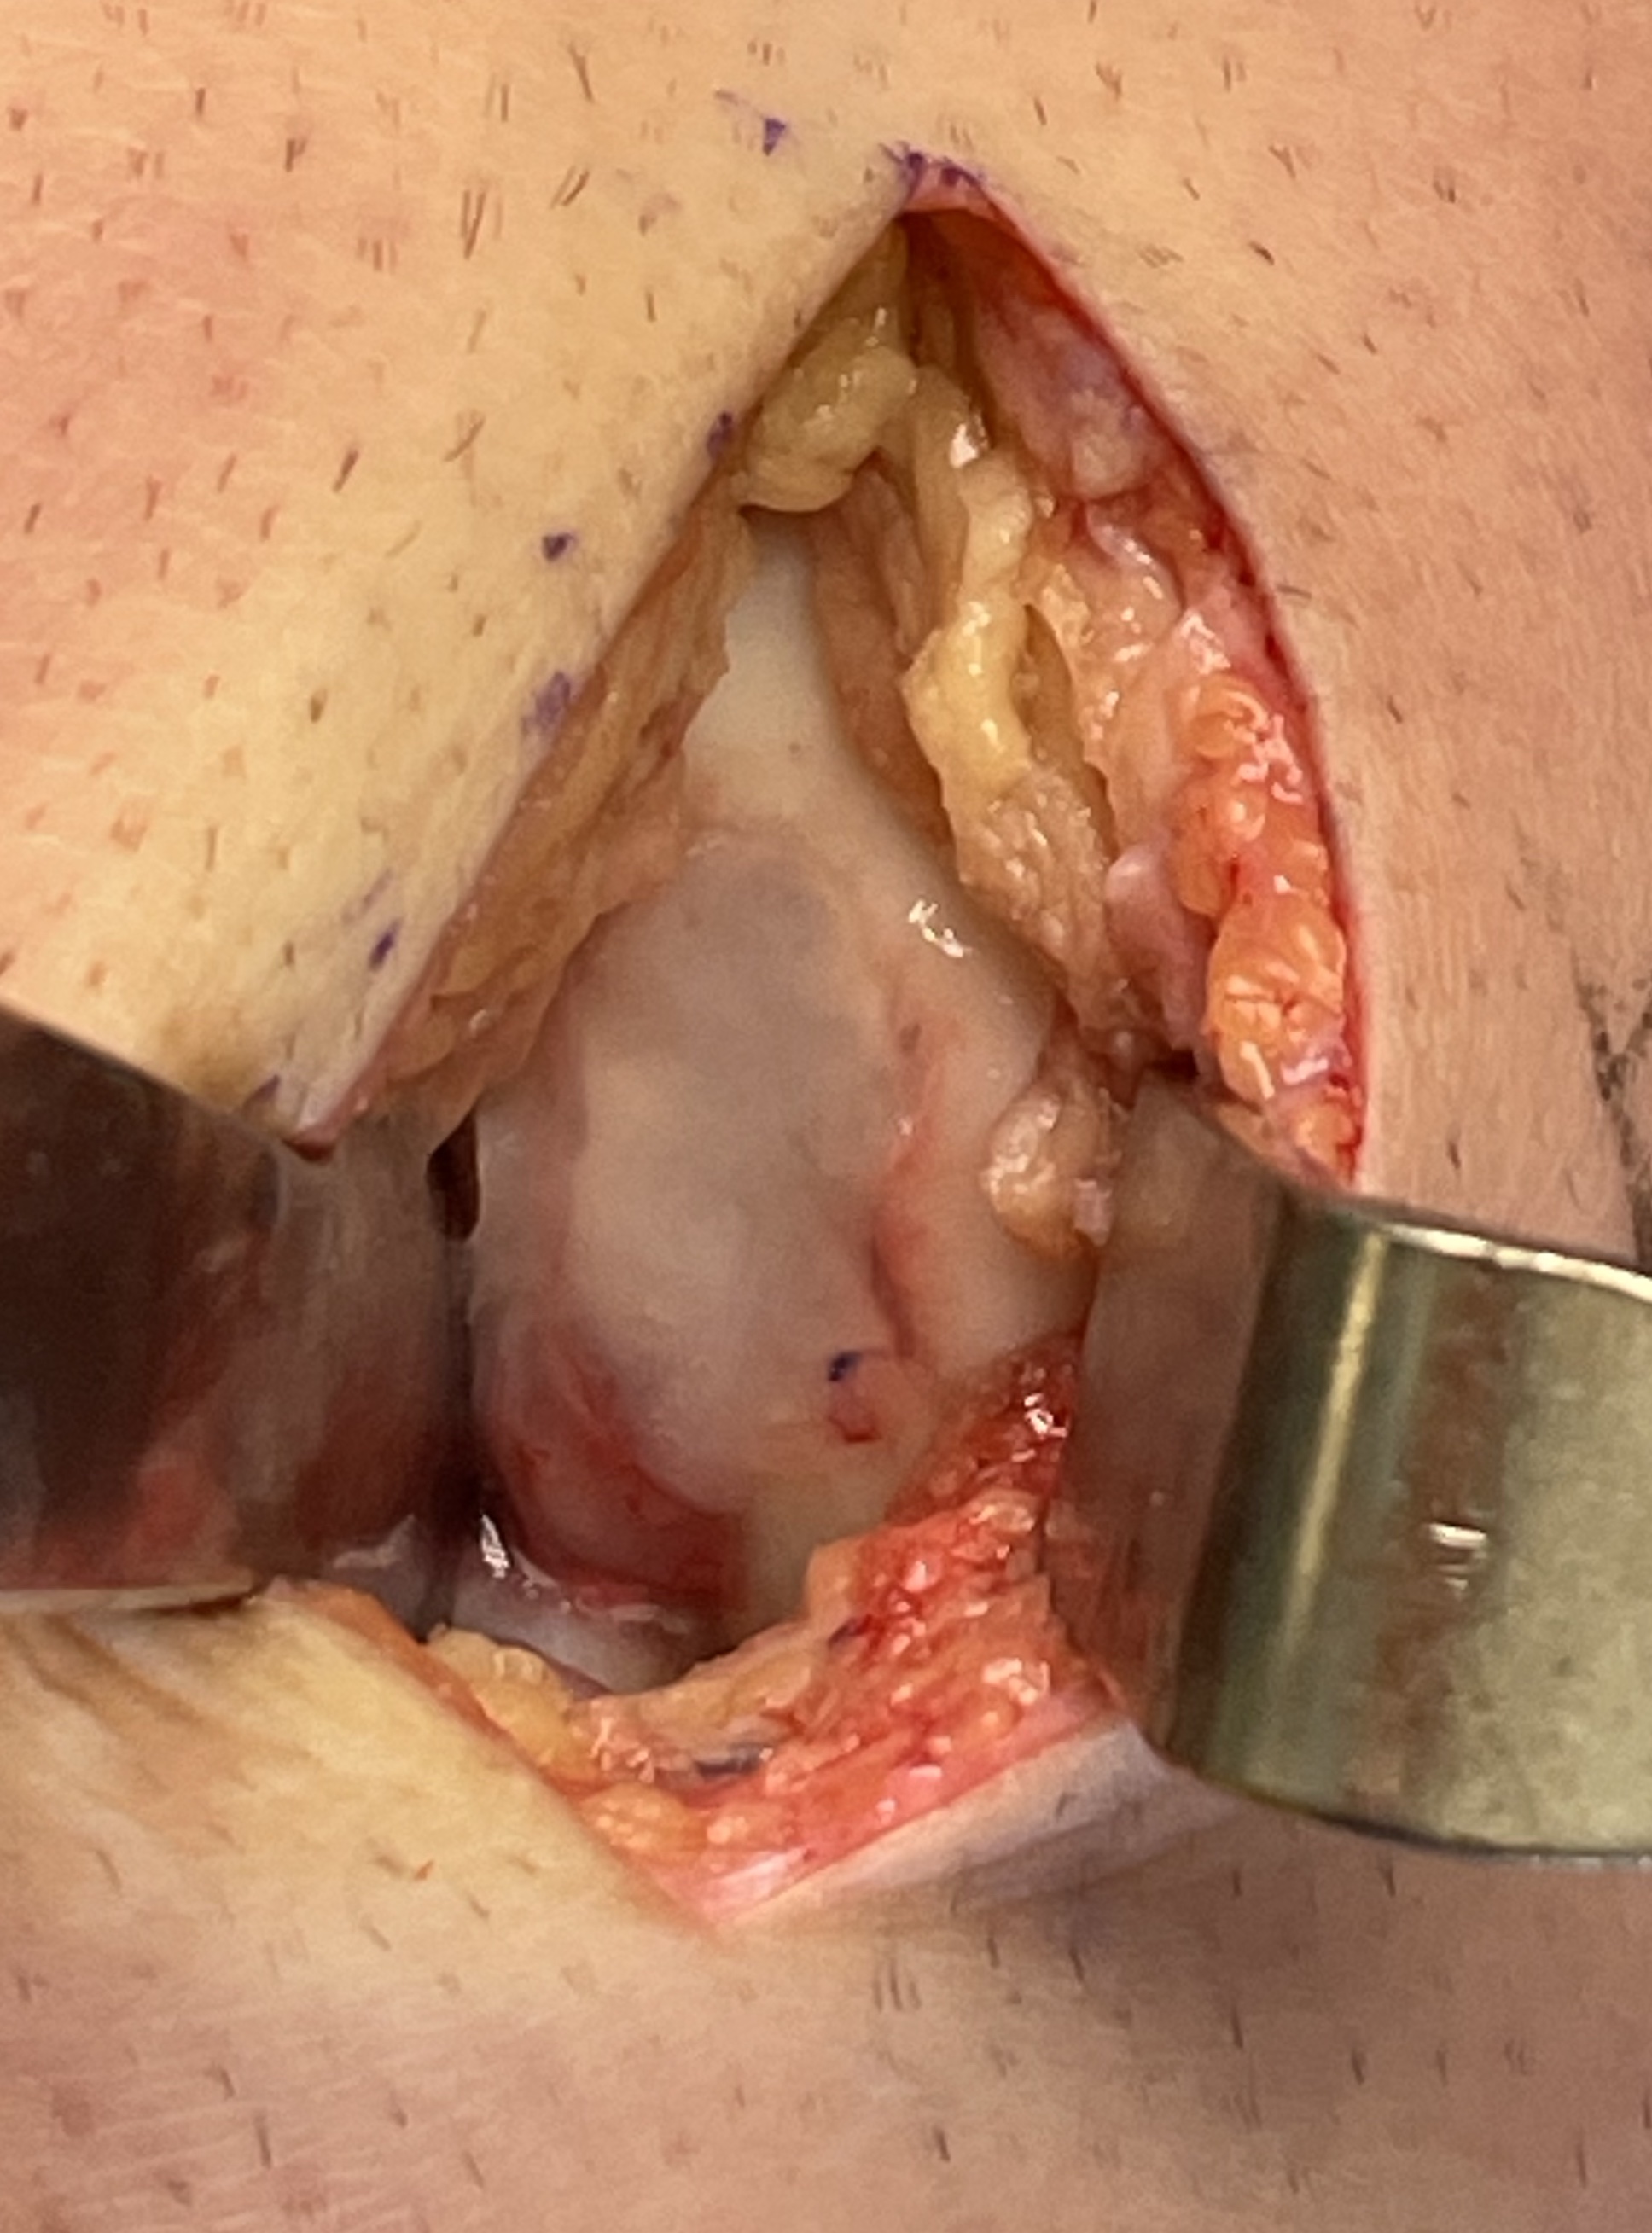

Debridement

Synovectomy / osteophyte removal / removal loose bodies

Osteochondral Autologous Transplantation (OATS)

Indication

Focal osteochondral defect

Donor site

Lateral trochlea of knee

Lateral articular surface talus

Autologous Matrix Induced Chondrogenesis (AMIC)

Concept

Microfracture with collagen patch

Interposition arthroplasty

Results

Cevik et al Foot Ankle Int 2020

- 24 cases advanced stage Freibergs

- interposition arthroplasty with EDB tendon

- 9 very satisfied, 12 satisfied, 2 moderately satisfied, 1 dissatisfied